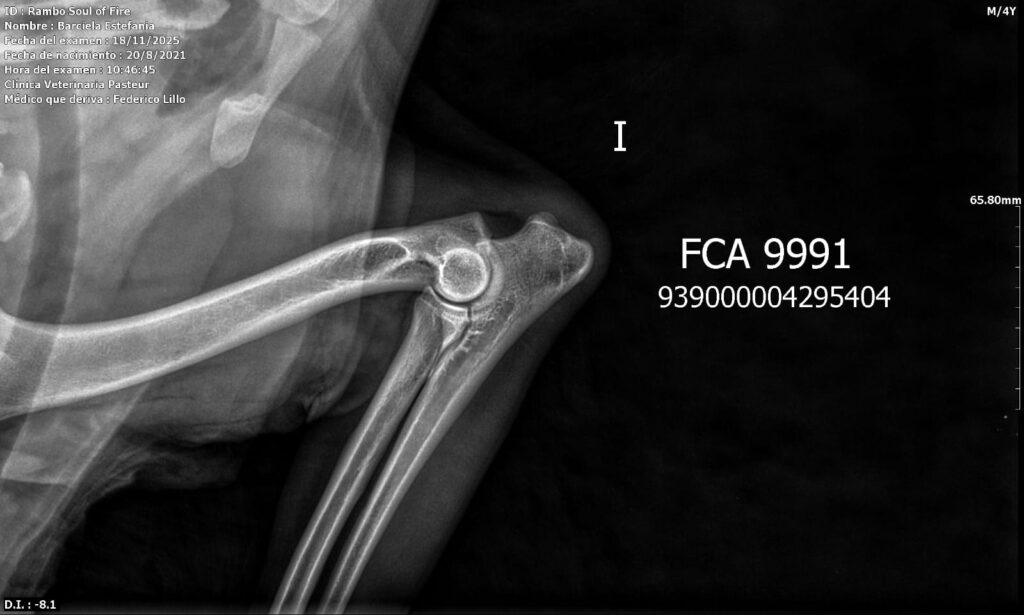

Placas de caderas y codos en La Rienda Border Collie

En La Rienda Border Collie la cría responsable no es un eslogan: es una forma de trabajar desde hace años. Por eso, nuestros machos reproductores y algunas de nuestras hembras cuentan con estudios radiológicos de caderas y codos, un paso clave para garantizar cachorros sanos, equilibrados y con una excelente calidad de vida.

Realizamos radiografías oficiales de caderas y codos a nuestros reproductores, evaluadas por profesionales veterinarios especializados.

Estos estudios permiten detectar posibles patologías hereditarias, como la displasia de cadera y de codo, ayudando a reducir su incidencia generación tras generación.

✔ Clasificación A en caderas y codos, indicativo de articulaciones sanas y excelente conformación

✔ Clasificación A en codos y B en caderas, siempre informada con total transparencia y criterio de selección responsable